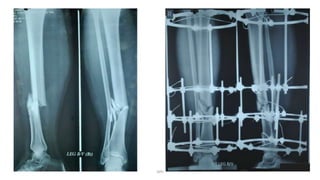

Nonunion

DPS